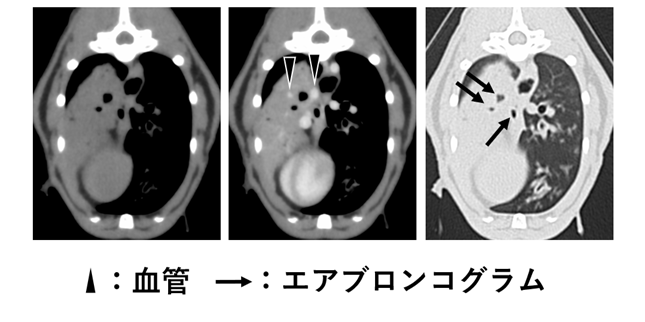

図:犬や猫における肺リンパ腫のCT所見

- 肺リンパ腫症例(犬1例、猫2例)を解析した結果、リンパ腫の輪郭が明瞭で均一に造影され、明確なエアブロンコグラムと肺血管が認められるという共通した特徴があることを明らかにした。

本研究では、2015年から2024年の間にCT検査を受けた肺病変が疑われる犬や猫を対象としました。組織学的解析により肺病変がリンパ腫と確定診断された症例を対象とし、複数の腫瘍を有する症例は除外しました。最終的に犬において1例、猫において2例が対象として同定されました。この3例を対象に、CT画像から肺病変の特徴について検討した結果、肺リンパ腫は輪郭が明瞭で均一に造影される特徴的な病変として描出されました。また病変内には明瞭なエアブロンコグラムと明確に描出される肺血管が認められました。

これらの結果より、病変内の明瞭なエアブロンコグラムや明確に描出される肺血管、均一な造影効果は、肺リンパ腫の同定に有用である可能性が示されました。